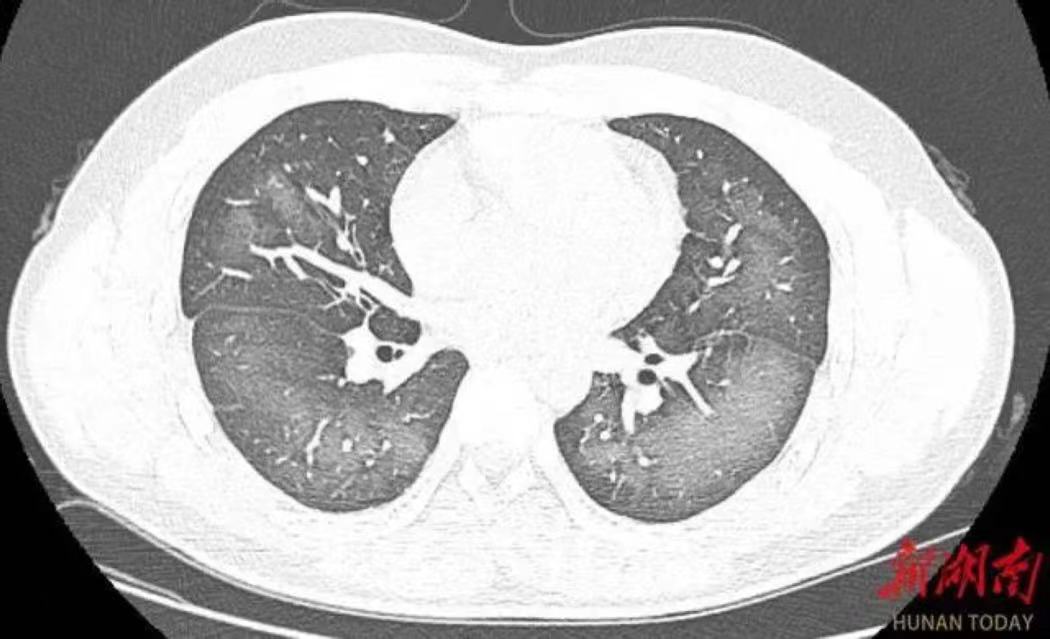

经检查,肺部CT片显示,李林双肺赫然呈现大范围白色样病变,报告提示“白肺”。

“白肺”一般是指重症肺炎在X线或CT检查下的表现,患者肺部呈现一大片的白色状态,往往会出现呼吸困难、呼吸衰竭,严重者还会出现其他脏器功能障碍。